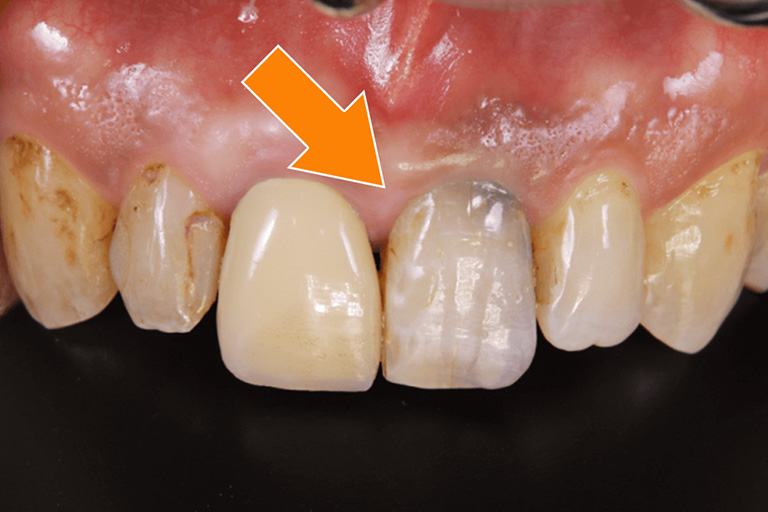

図2

矢印に示す歯は人工の被せ物が装着されています。この歯も同様に他の歯のホワイトニング後、被せ物を新しく作り直す必要があります。

図3

矢印に示す歯は、人工物は装着されていませんが、過去の歯の根の治療がきっかけで、内部から着色しています。この場合、ホワイトニングの効果がないので、インターナルブリーチという方法や、被せ物を装着して歯の内部の色を遮断する必要があります。